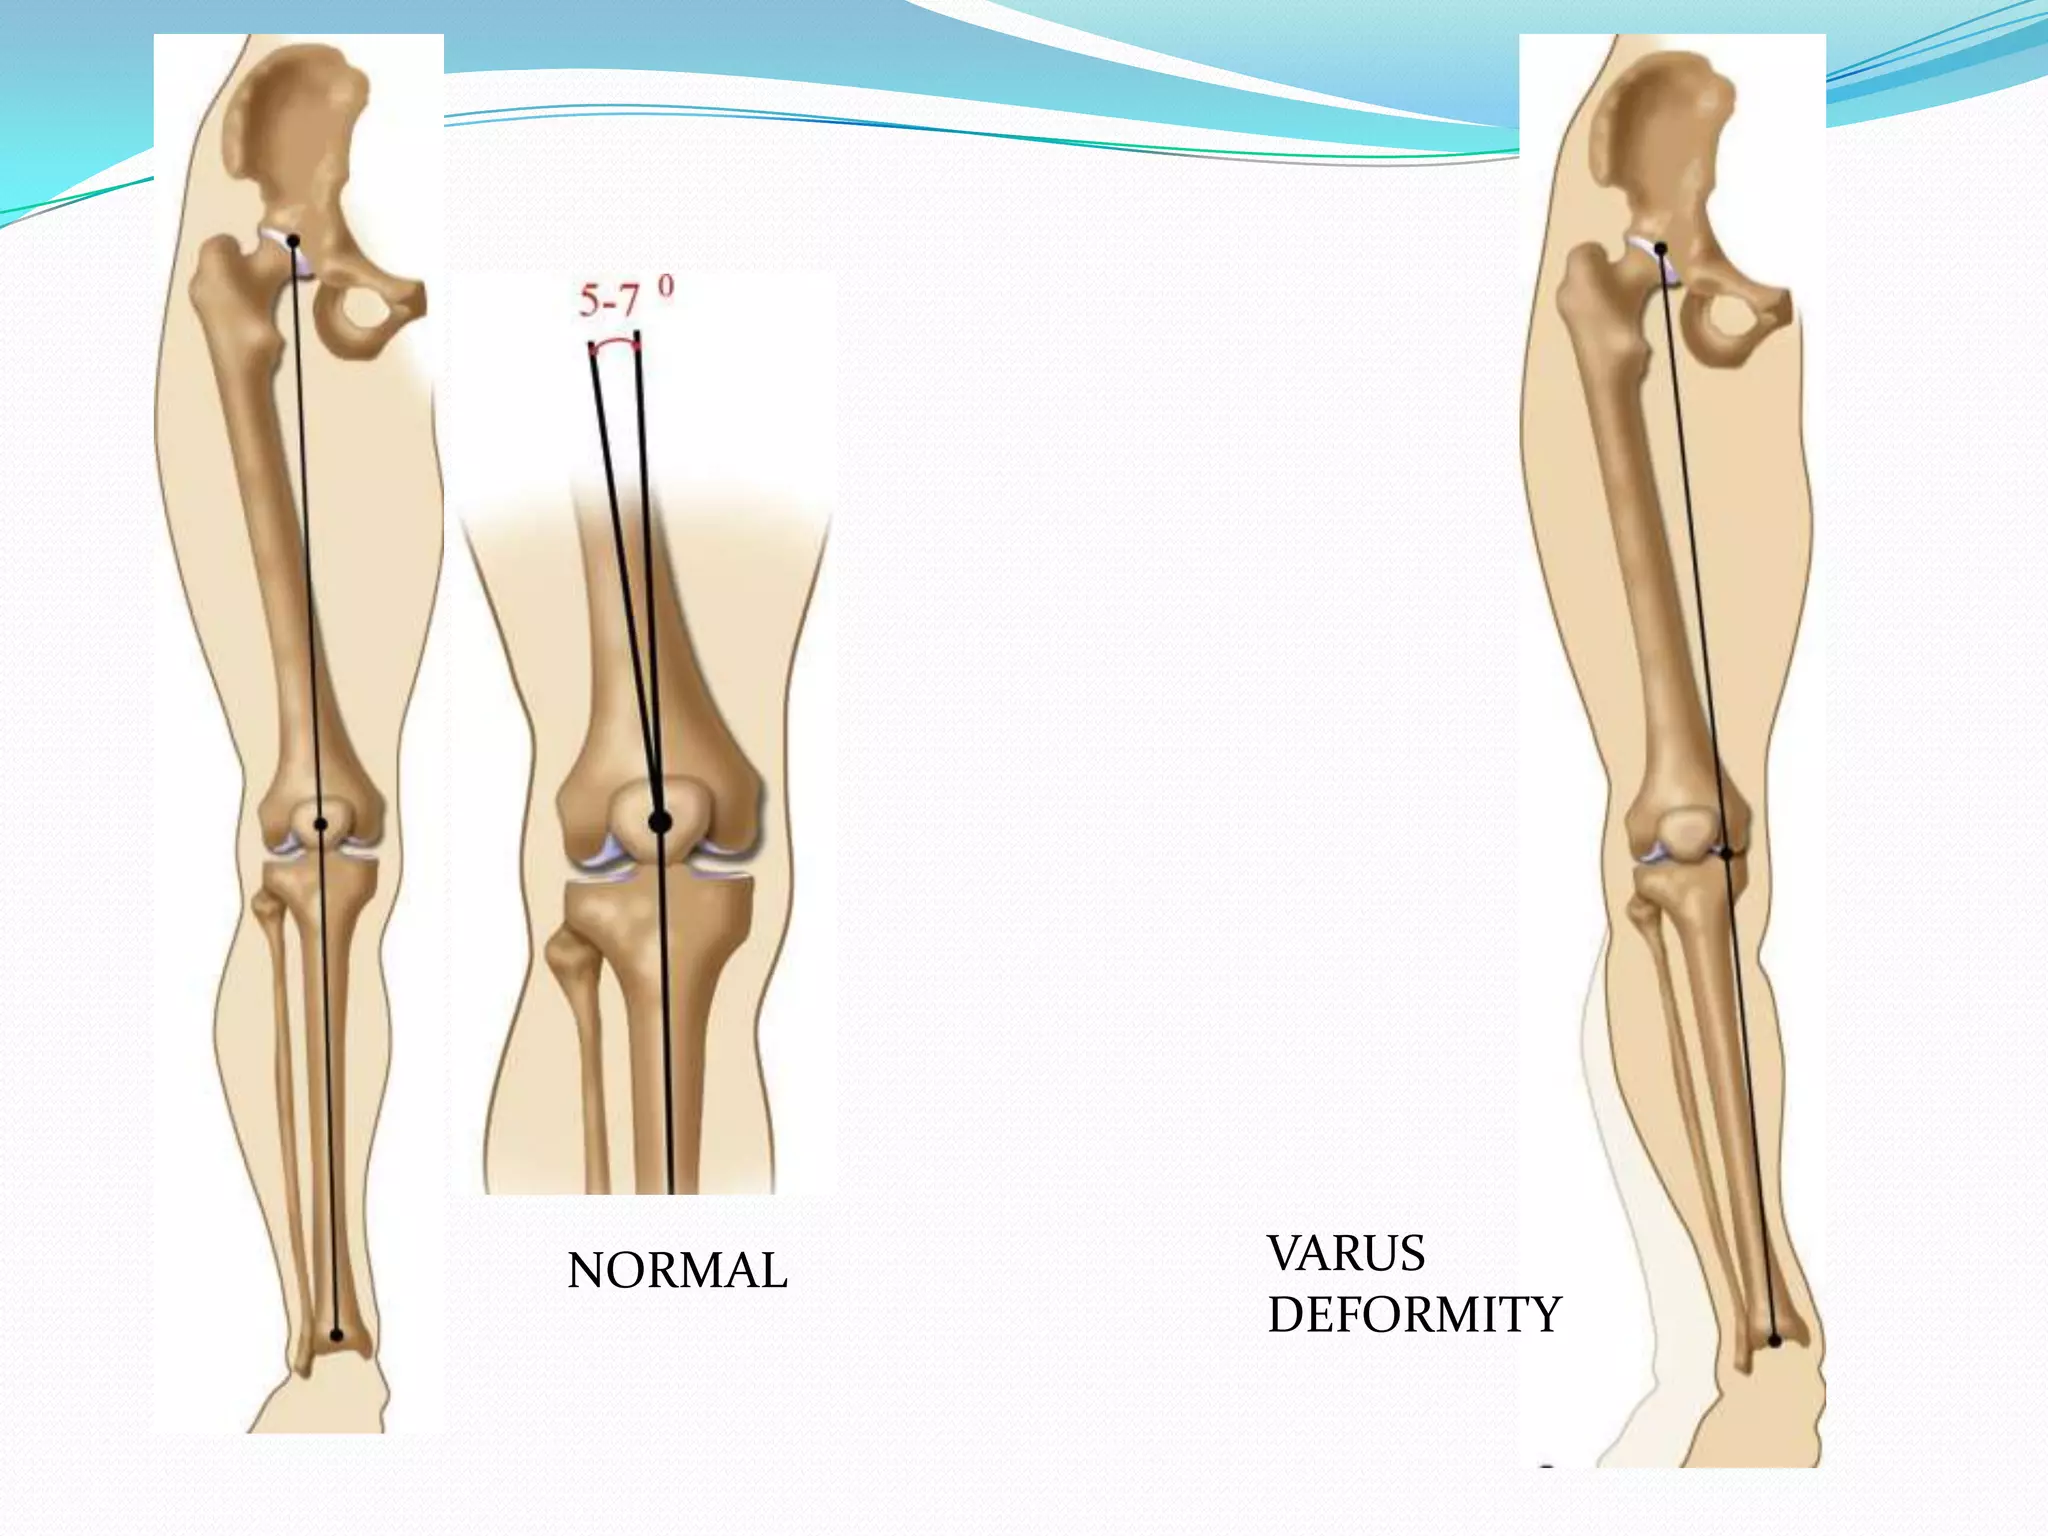

NORMAL VARUS

DEFORMITY

Load sharing by the medial and

lateral compartment

Position % weight through medial comp

Normal i.e. 2˚ varus 75 %

Centre 70%

4˚ valgus 50%

6˚ valgus 40%

3˚-6˚ mechanical valgus is recommended for treatment of MCOA

Load sharing bythe medial and lateral compartment Position % weight through medial comp Normal i.e. 2˚ varus 75 % Centre 70% 4˚ valgus 50% 6˚ valgus 40% 3˚-6˚ mechanical valgus is recommended for treatment of MCOA